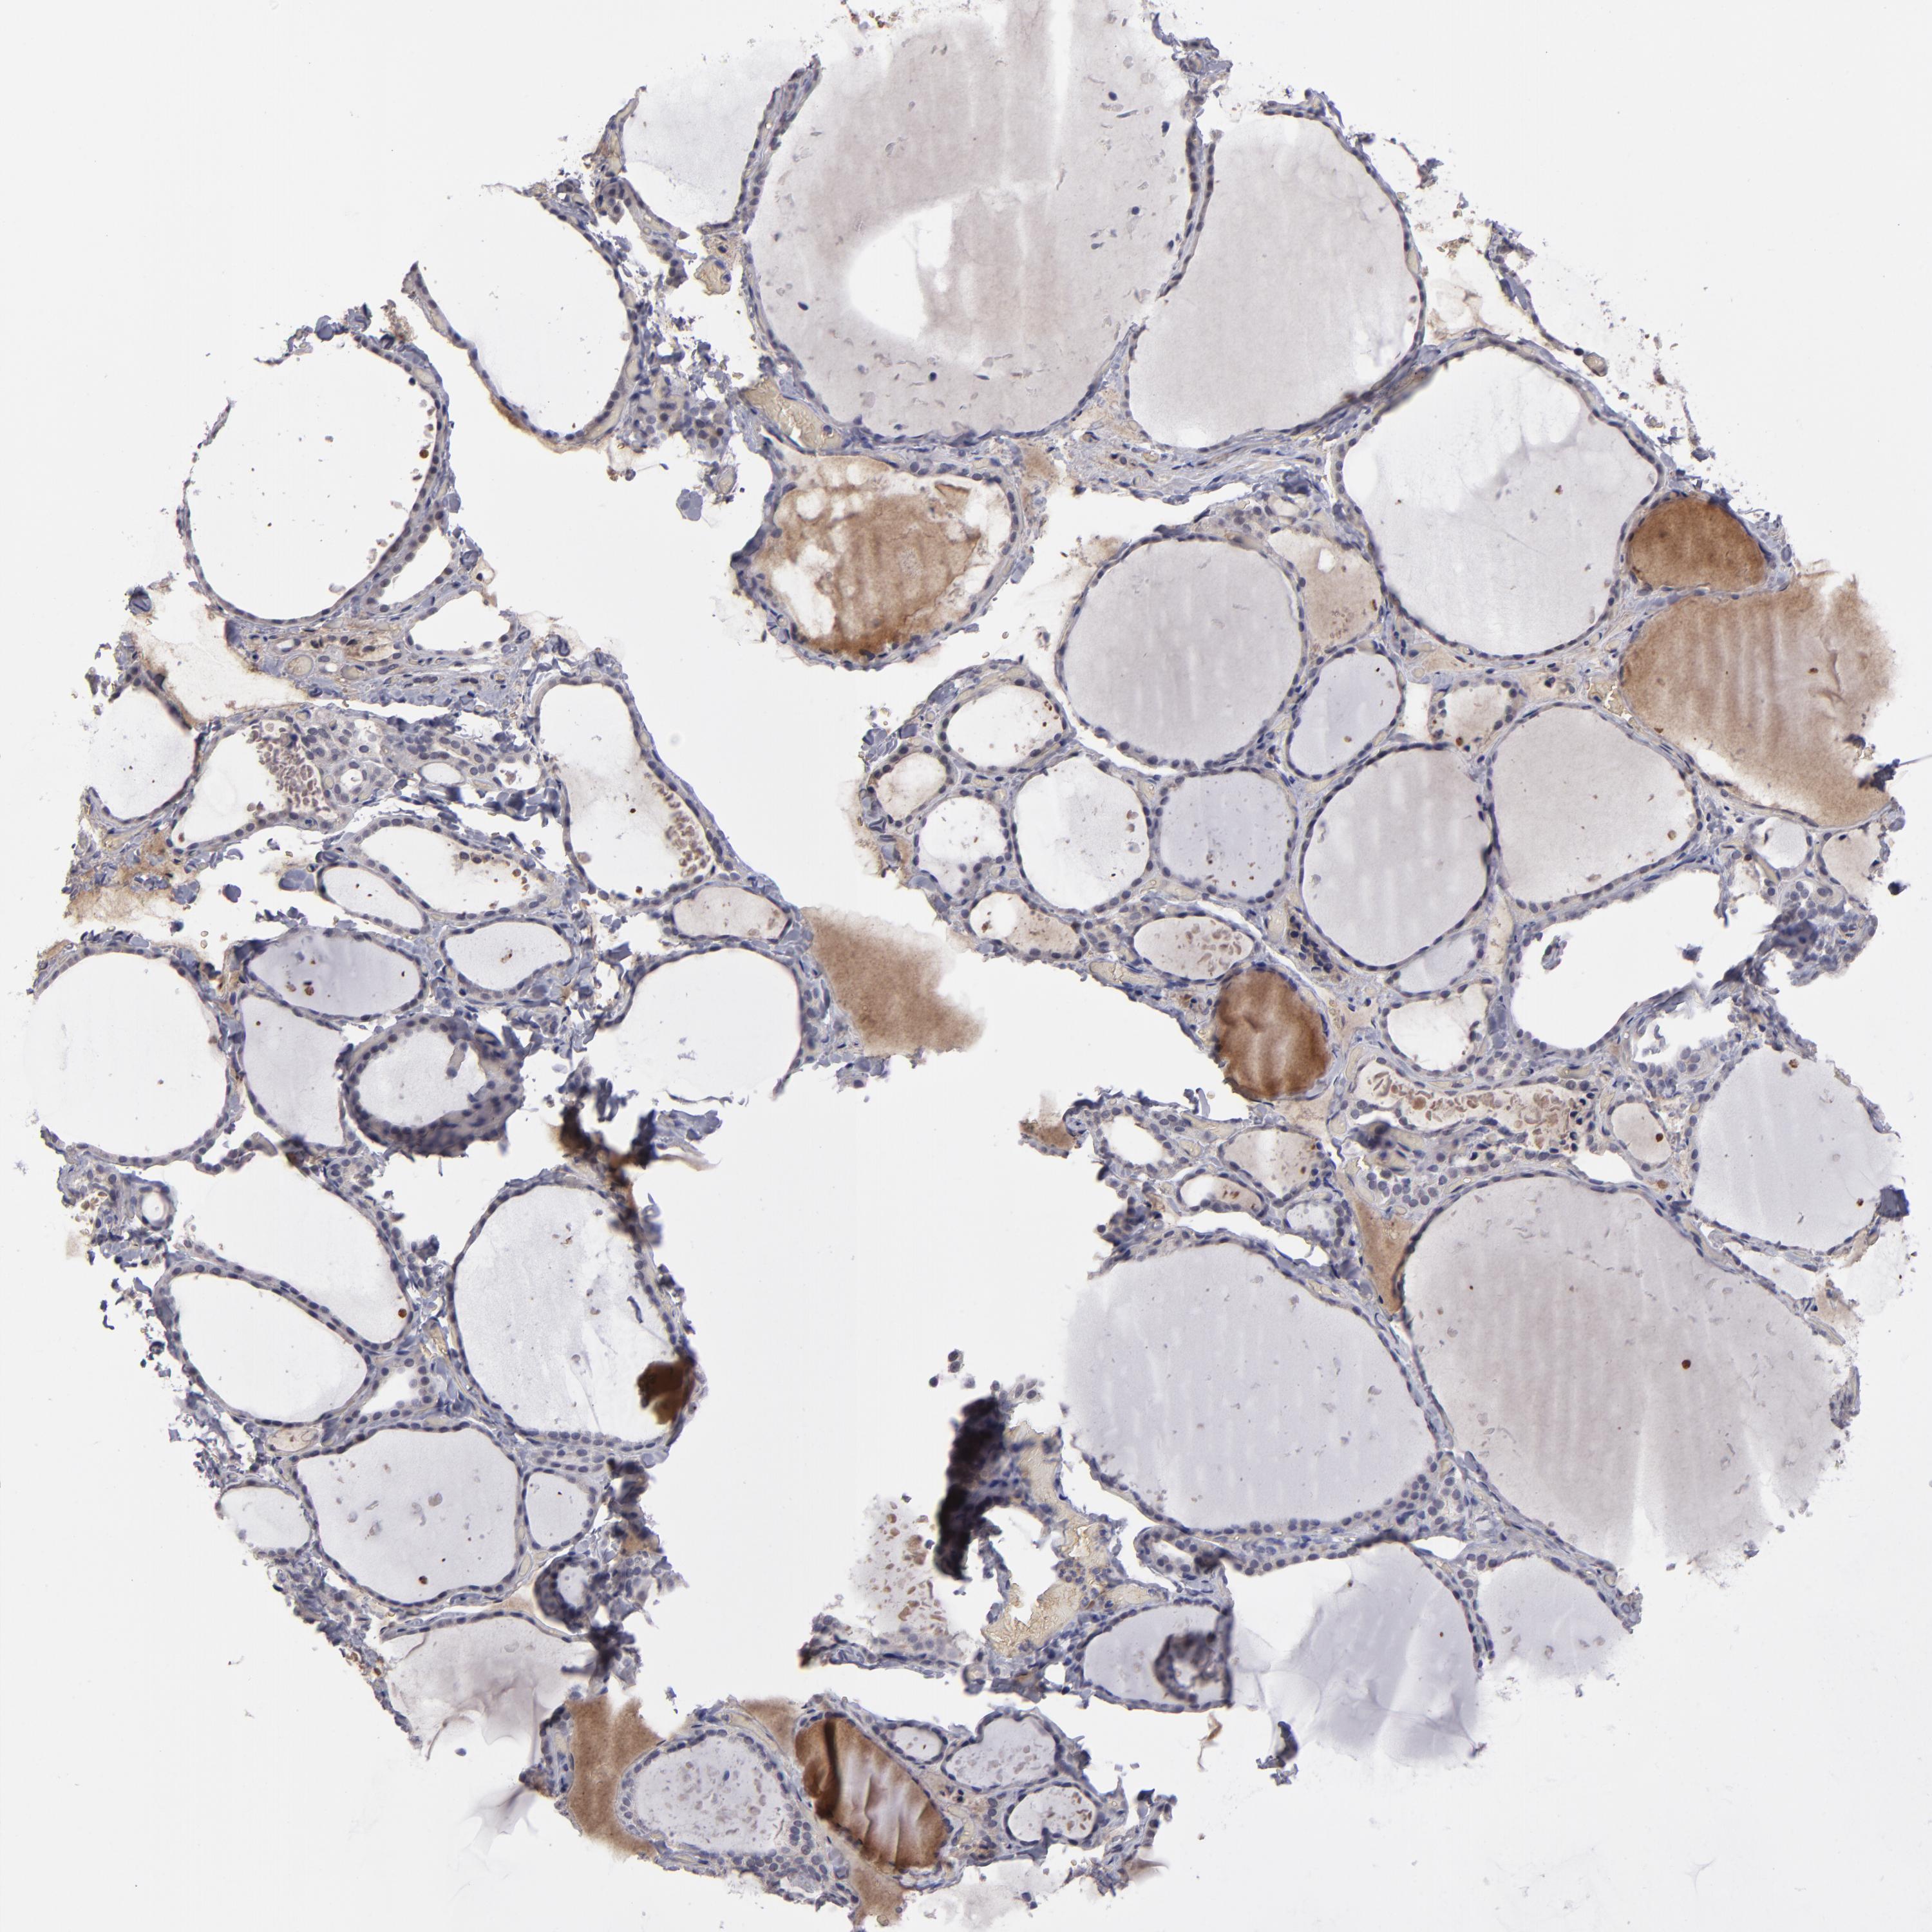

TISSUE PRIMARY DATA THYROID GLAND Show tissue menu

THYROID GLAND - Antibody stainingi

Antibody staining in the annotated cell types in the current human tissue is reported as not detected, low, medium, or high, based on conventional immunohistochemistry profiling in selected tissues. This score is based on the combination of the staining intensity and fraction of stained cells.

Each image is clickable and will lead to virtual microscopy that enables deeper exploration of all samples and also displays staining intensity scores, fraction scores and subcellular localization as well as patient and tissue information for each sample.

Antibody HPA001835Antibody HPA003948Antibody CAB072872

Glandular cells Not detectedNot detectedNot detected